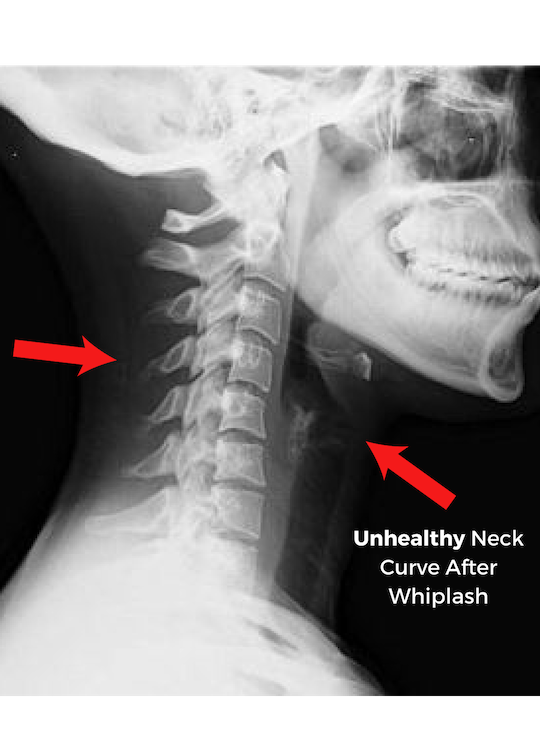

•  Whiplash is the single greatest threat to auto-accident individuals.

•  Untreated whiplash can cause long-term health complications, neck & back strain, nausea, dizziness, severe migraines, & radiating pain across the upper body.

Spinal problems can go unnoticed for months...

and then out of the blue cause debilitating health complications.